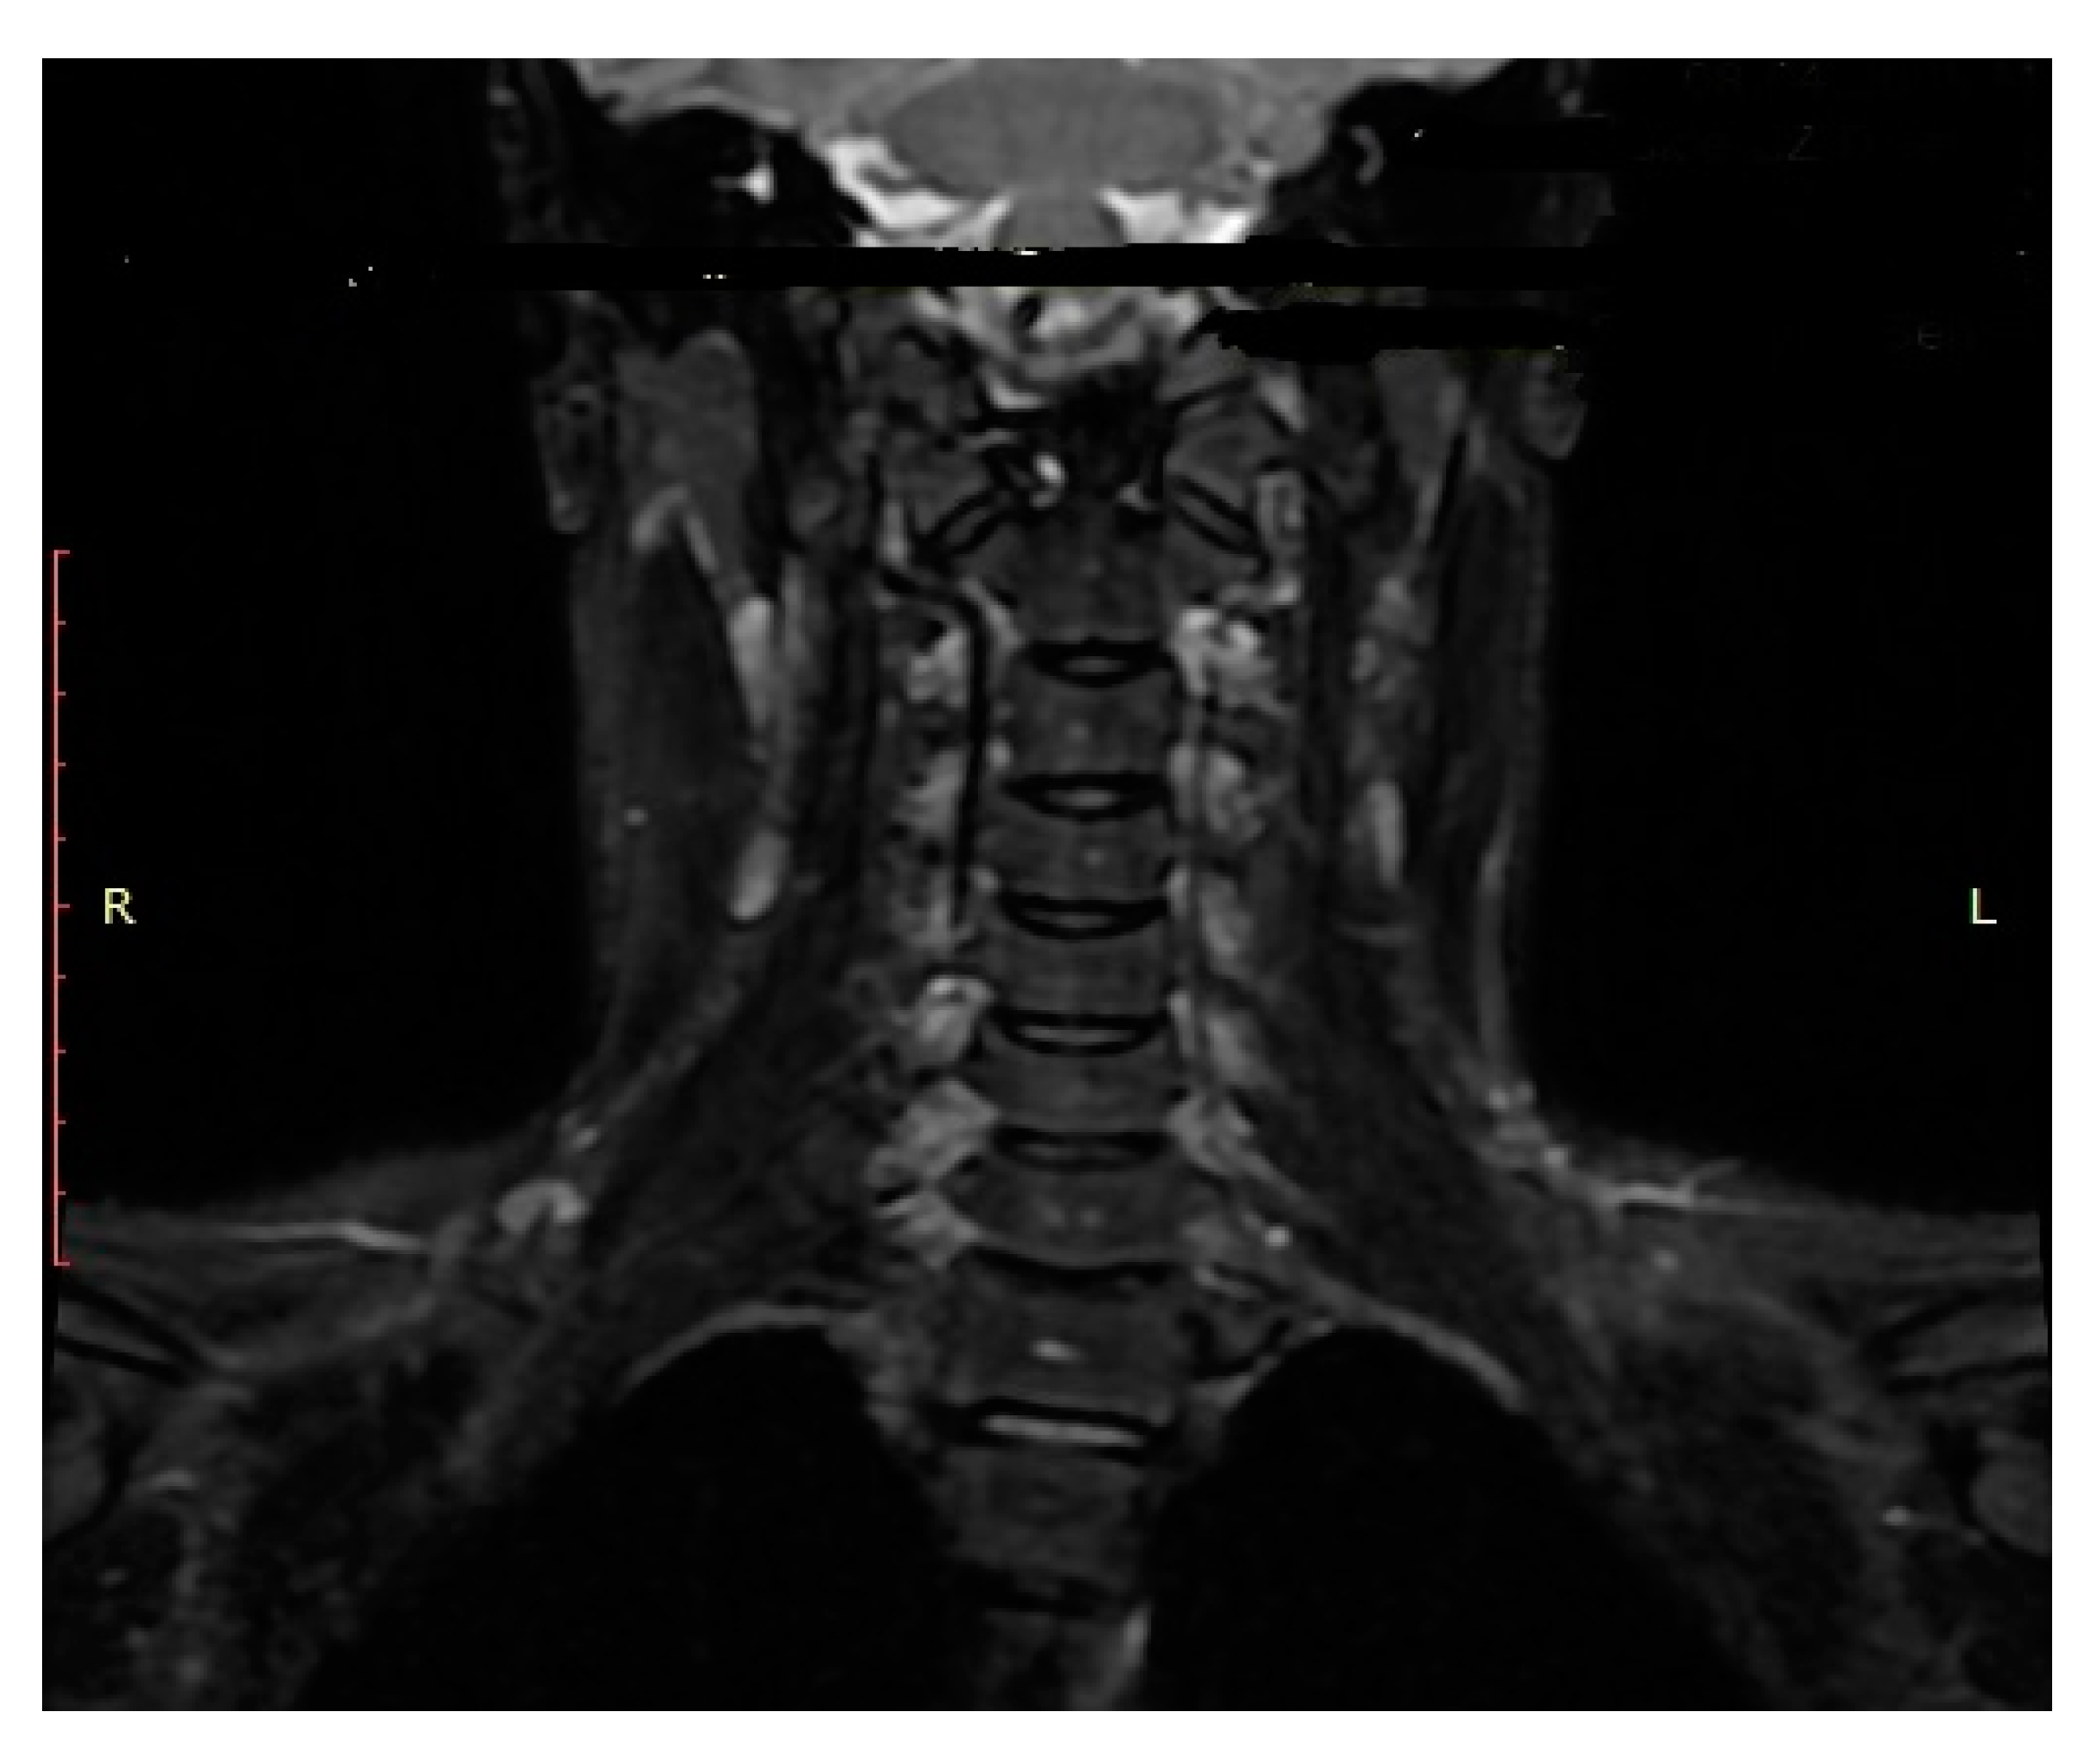

- We recommend CT and MRI of the CCJ to diagnose OCF and confirm post-therapeutic fracture consolidation in pediatric patients.

- Roy, A.K.; Miller, B.A.; Holland, C.M.; Fountain, A.J.; Pradilla, G.; Ahmad, F.U. Magnetic resonance imaging of traumatic injury to the craniovertebral junction: A case-based review. Neurosurg. Focus 2015, 38, E3. [Google Scholar] [CrossRef] [Green Version]